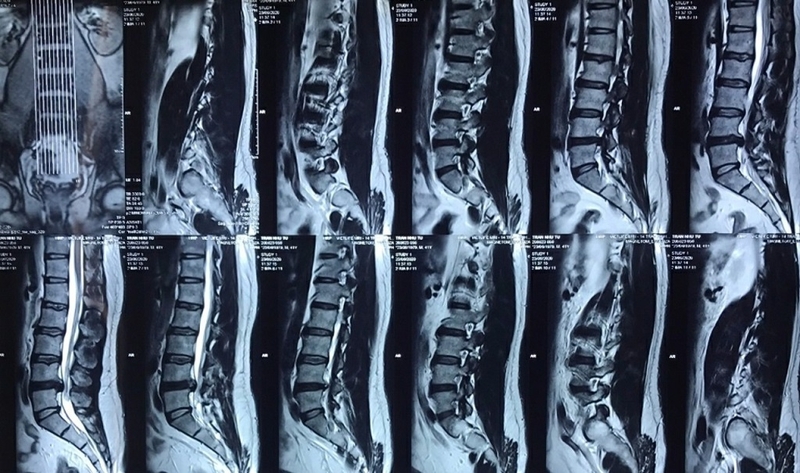

Phẫu thuật hẹp ống sống diễn ra như thế nào? Khi nào cần phẫu thuật?

Phần cột sống nâng đỡ cơ thể con người có cấu tạo gồm nhiều đốt sống, đan xen vào đó là các đĩa đệm giảm sốc. Trên mỗi đốt sống là một lỗ sống để tủy sống và các rễ thần kinh đi qua. Các đốt sống xếp chồng lên nhau, các lỗ sống sẽ tạo thành những khoang rỗng xuyên suốt từ cột sống, chúng được gọi là ống sống.

Tình trạng các khoang rỗng bị thu hẹp lại, tạo áp lực lên dây thần kinh và tủy sống được gọi là hẹp ống sống. Các đối tượng trên 50 tuổi thường gặp phải tình trạng này với nhiều triệu chứng khác nhau như tê vai, mỏi cổ, đau lưng, đau từ vùng hông xuống hai chân, rối loạn cơ tròn, bí tiểu, liệt nửa người, liệt hoàn toàn hoặc liệt tứ chi

Phẫu thuật hẹp ống sống diễn ra như thế nào?

Khi các phương pháp điều trị nội khoa không mang đến hiệu quả, không làm cải thiện triệu chứng ngay cả khi đã kết hợp với các phương pháp điều trị bảo tồn như uống thuốc, vật lý trị liệu, kéo giãn cột sống thì bác sĩ sẽ cho người bệnh tiến hành phẫu thuật với các phương pháp phổ biến bao gồm:

• Phẫu thuật giải ép thần kinh nhằm mục đích làm rộng ống sống.

• Phẫu thuật loại bỏ đĩa đệm kết hợp với việc hàn xương.

• Phẫu thuật hỗ trợ cột sống liên gai bằng cách đặt thêm dụng cụ hỗ trợ.

• Phẫu thuật nội soi mở cửa sổ xương giải ép ống sống.